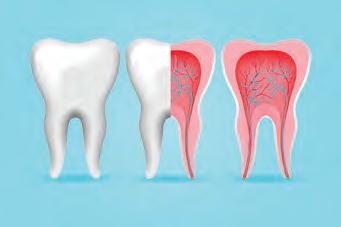

Кариес

ечение в запущенных случаях начинается с депульпации (удаление нерва) Эта процедура поможетет ликвидировать воспаление

внутрь различным бактериям.

При кариесе или других подобных проблемах нерв начинает реагировать на внешние раздражители и человек чувствует боль. Часто лечение зуба без извлечения пульпы провести невозможно. Поэтому стоматолог

В КАКИХ СЛУЧАЯХ НЕОБХОДИМО УДАЛЯТЬ